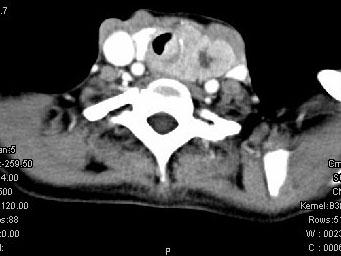

问题 女,50岁,左下颈部扪及一质硬、表面高低不平的包块,肿块逐渐增大,现感吞咽困难,CT如图所示,最可能诊断为 ( )

选项 A、甲状腺原发淋巴瘤 B、颈部神经鞘瘤 C、食管癌 D、喉癌 E、甲状腺癌

答案 E